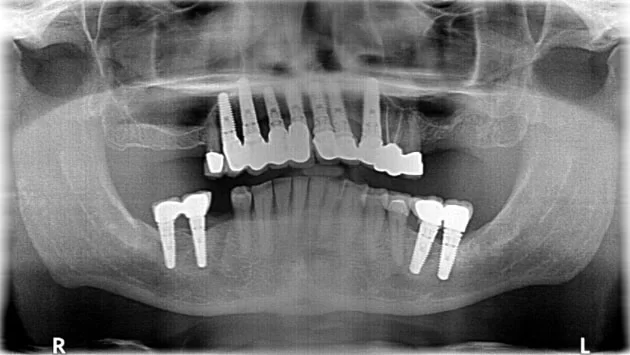

5. Colocación de la prótesis

El especialista destapa la encía para exponer los implantes. Aquí se colocan las coronas, puentes o dentaduras, según lo que necesites.

En X Dentistry, nuestros especialistas son verdaderos artesanos dentales. Con un proceso detallado y preciso, y utilizando materiales y tecnologías de última generación como Nobel Biocare, Straumann y Bicon, logramos resultados estéticos naturales que superan las expectativas.